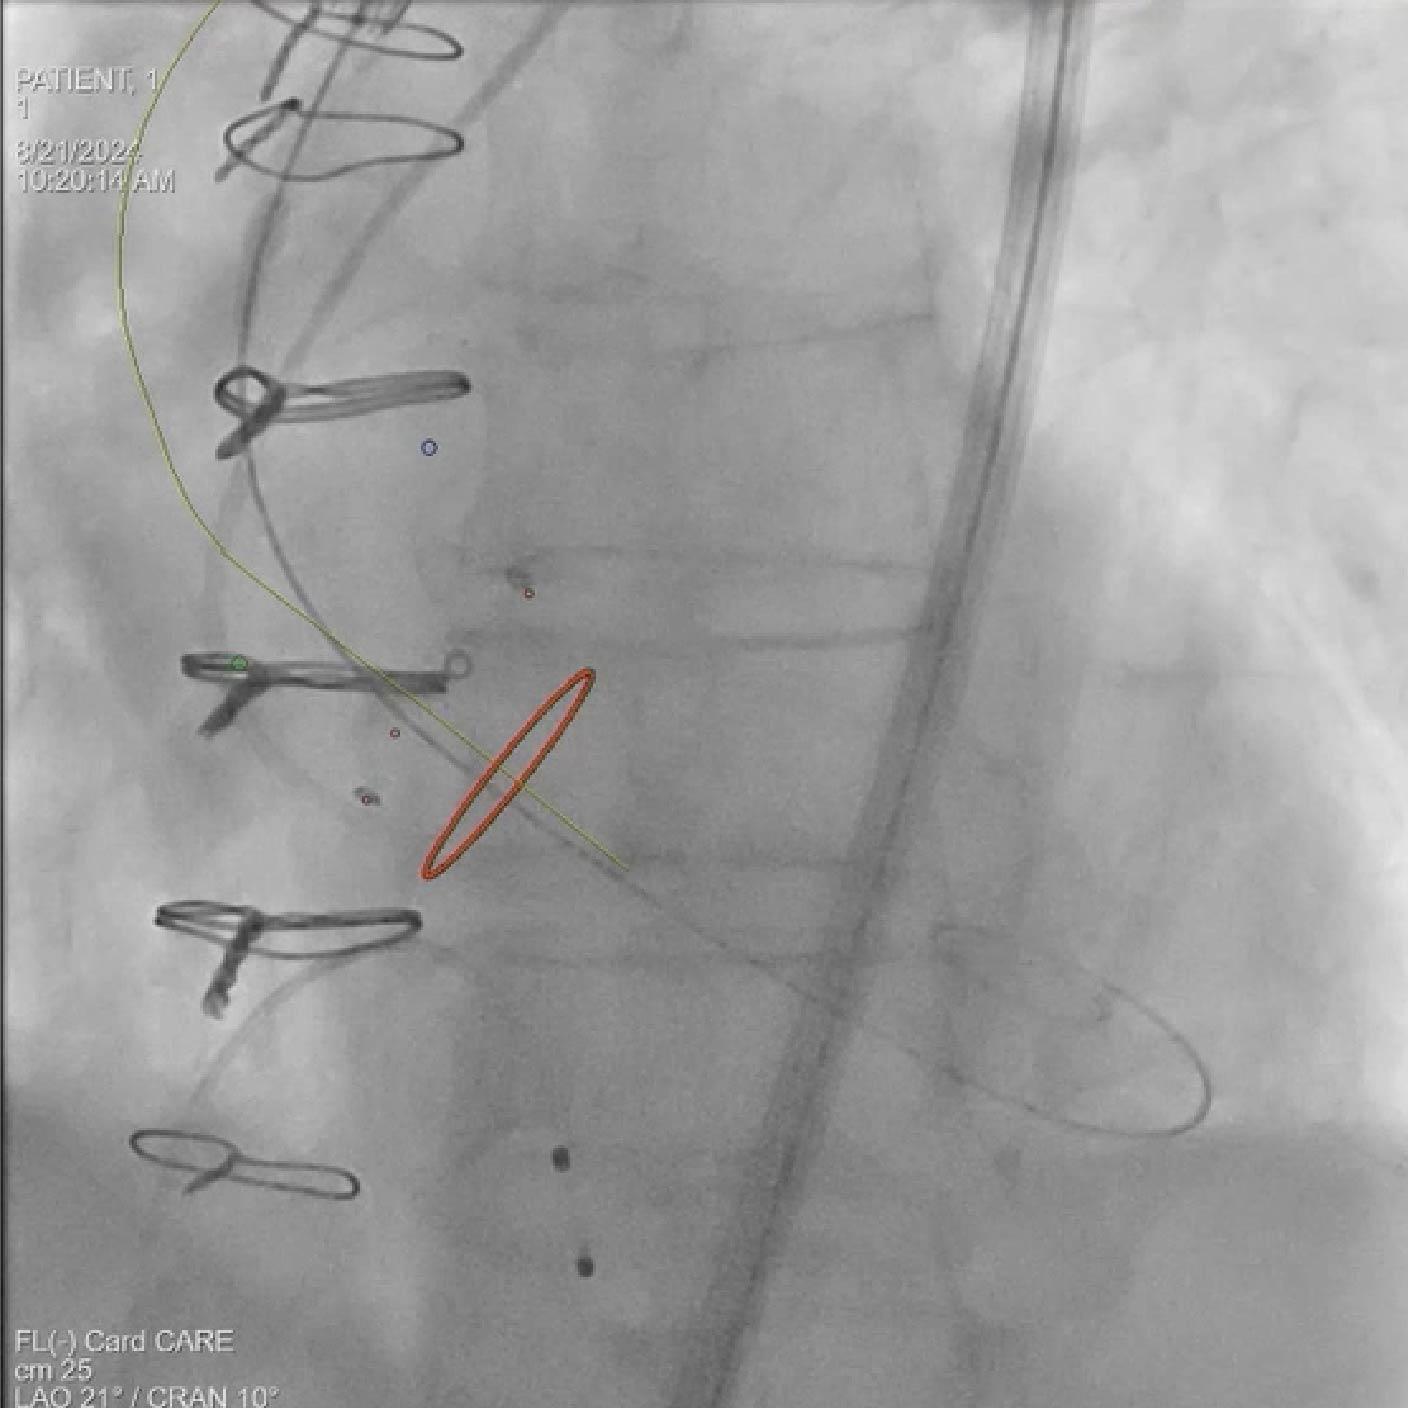

- Colocación del guía y del dispositivo con syngo Aortic Valve Guidance

Soluciones y características seleccionadas: ARTIS pheno, Case Flows, Una combinación preestablecida de configuraciones (angulación, disposición de la pantalla, etc.), personalizada para la colocación del dispositivo SENTINEL™*, reduce las interacciones con el sistema. Con Case Flows, una única interacción del usuario reemplaza el ajuste de hasta 6 configuraciones del sistema³. syngo 2D/3D Fusion - Aplicación para superponer la anatomía de la arco aórtico basada en tomografía computarizada sobre fluoroscopia en vivo, para apoyar la navegación del dispositivo. Se ha demostrado que la guía por fusión reduce significativamente el tiempo de despliegue del dispositivo SENTINEL™* y el uso de contraste⁴.

Soluciones y características seleccionadas: 3mensio (Pie Medical Imaging) Software semiautomatizado para asistir en la reconstrucción 3D de la válvula previamente implantada y la anatomía circundante, con el fin de determinar el abordaje ideal y el tamaño adecuado de la válvula. Su uso reduce el tiempo de planificación del TAVR¹ y los resultados de la planificación pueden exportarse para superposición en tiempo real durante la fluoroscopia.